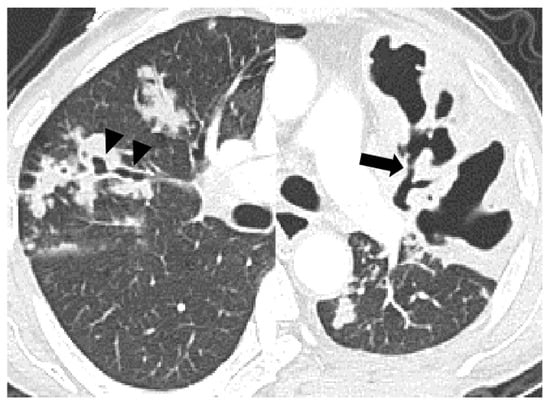

4. Discussion